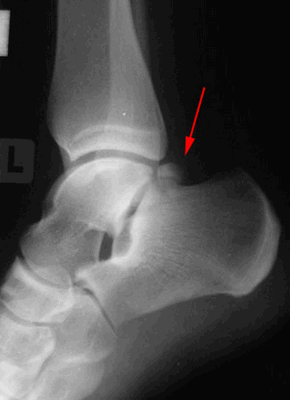

Рентгенограммы пациента с задним импиджмент синдромом

Выполняются рентгенограммы голеностопного сустава в двух проекциях. На обычных рентгенограммах остеофиты (костные шпоры) на голени или таранной кости чётко определяются. Можно выполнить боковые стресс-рентгенограммы, когда при приседании на корточки можно выявить соударение костных поверхностей в передней части голеностопного сустава, а при вставании на носки - соударение в задних структурах голеностопного сустава.